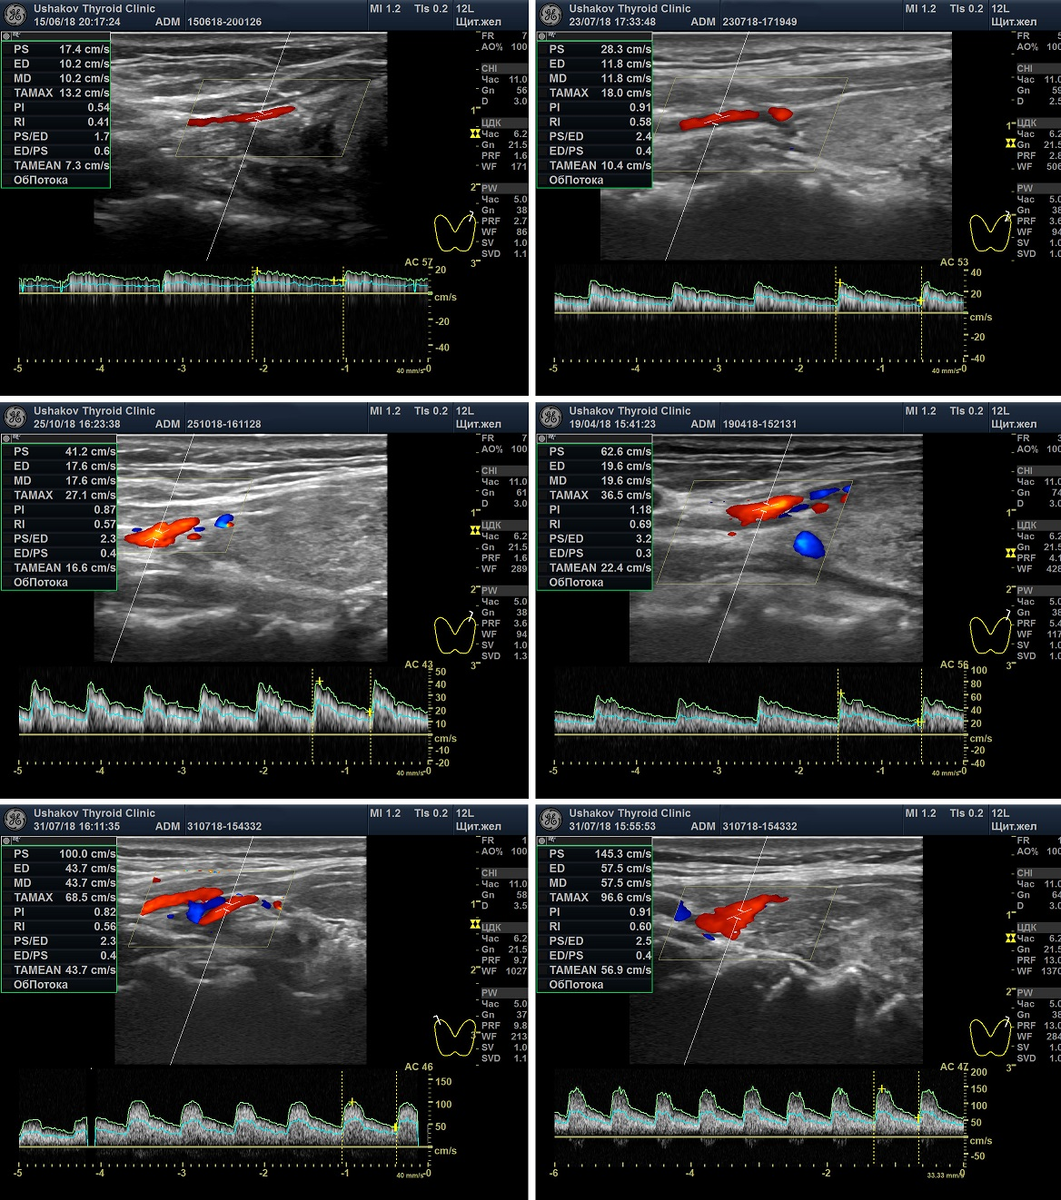

Очень важно в режиме ЦДК или ЭДК при УЗИ определить величину интенсивности кровотока. Не просто - "без изменения" или увеличен, а насколько увеличен.

Интенсивность кровотока (врачи пишут - васкуляризация) прямо указывает ан величину напряжения щитовидной железы!!! Это исследование не проводят около 50-60% узистов и ошибочно выполняют 40-49% других врачей УЗД. Не сопровождают Протоколы УЗИ снимками о кровотоке где-то 95% специалистов УЗИ.

Скорость кровотока (максимальная) в артериях щитовидной железы также показывает величину напряжения щитовидной железы (соответственно, её истощения!!!).